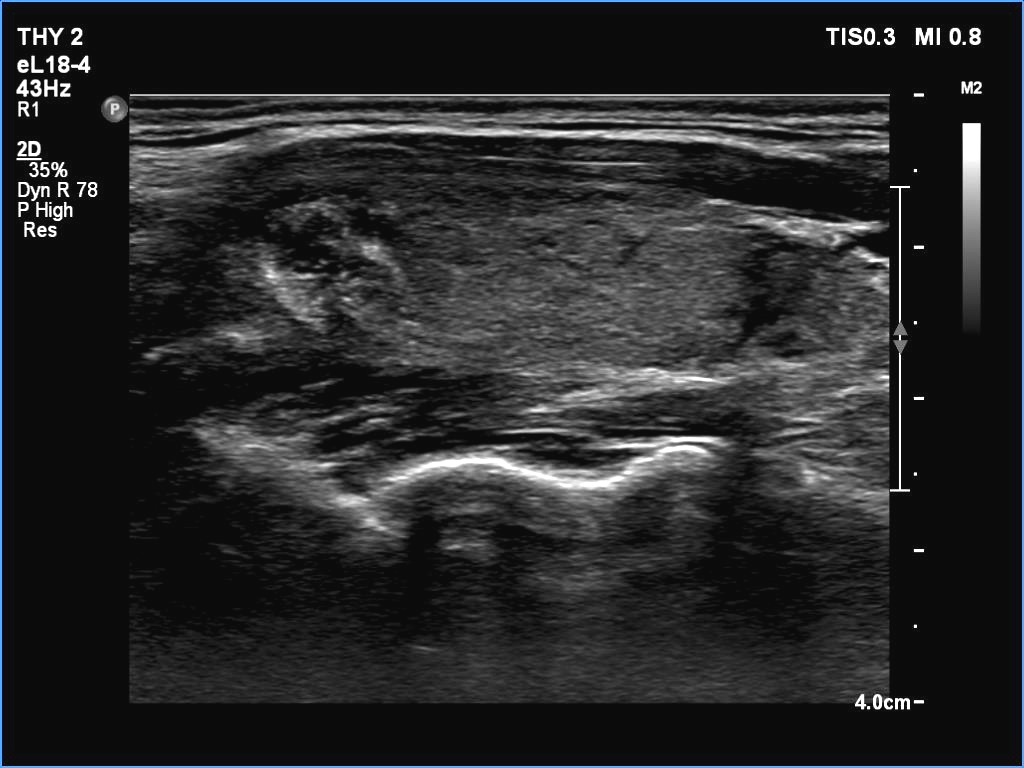

Ultrasonography. The thyroid was echonormal. There were two partly deeply hypoechoic nodules, one in the ventrolateral part of the right lobe and another one in the isthmus. Both had irregular margins and punctate echogenic foci. There was a mirror image artifact of the lesion in the isthmus.

Both nodules had multiple suspicious features: beside deep hypoechogenicity and irregular borders, microcalcifications should be also considered. The nodule in the right lobe presented also three possible sonographic signs of a possible extrathyroidal spread: the pseudocapsule of the thyroid was not intact, the lesion had both abutting and butting contours.